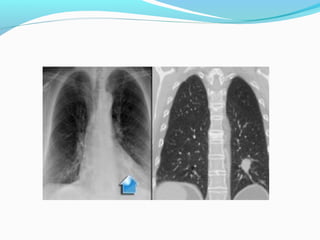

Alveolar cell carcinoma:

5% of lung tumours

Arises in the distal airways

Often diffuse, multifocal and bilateral

Resistant to radio-/chemotherapy

Very poor prognosis